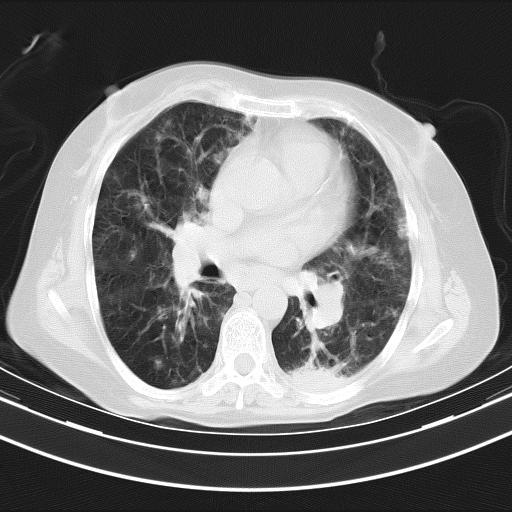

老年女性,嗜睡3天,意识模糊。轻咳,无发热。

两肺慢支炎伴感染,左侧胸腔积液。纵膈及双侧肺门淋巴结肿大建议复查。

双肺多发淡片影,毛玻璃影,,支持支气管肺炎,,建议血气找原因,,嗜睡是否肺性脑病?有没有慢支病史?

双肺炎症,建议抗炎治疗后复查,见过几个老年肺炎病例,没有发烧、咳嗽症状,直接以昏迷就诊。

1)两肺感染性病变;建议抗炎治疗后复查。2)纵隔淋巴结肿大。3)左侧胸腔积液。